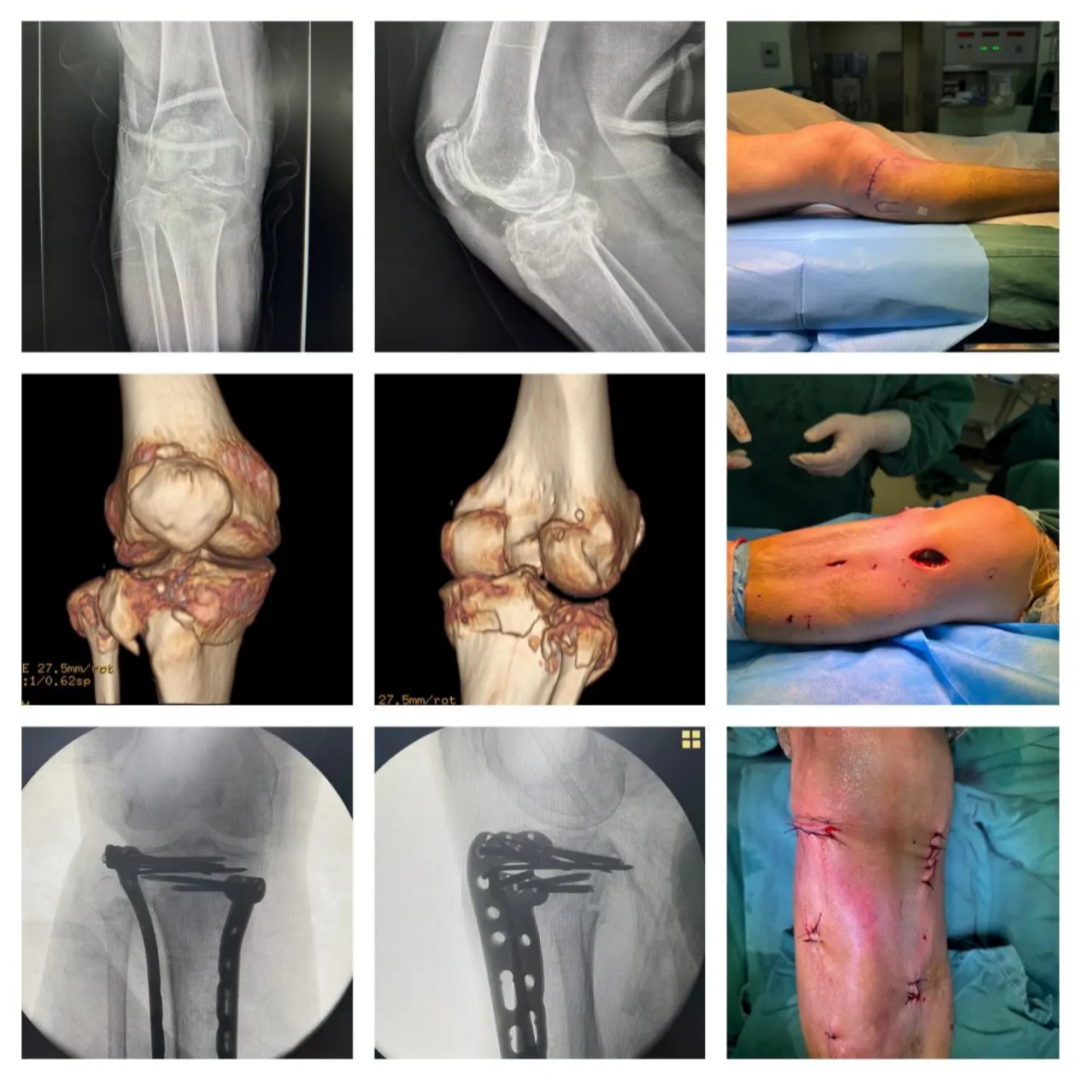

1.Case.01:68 岁,男性。左胫骨平台骨折(Schatzker V 型)